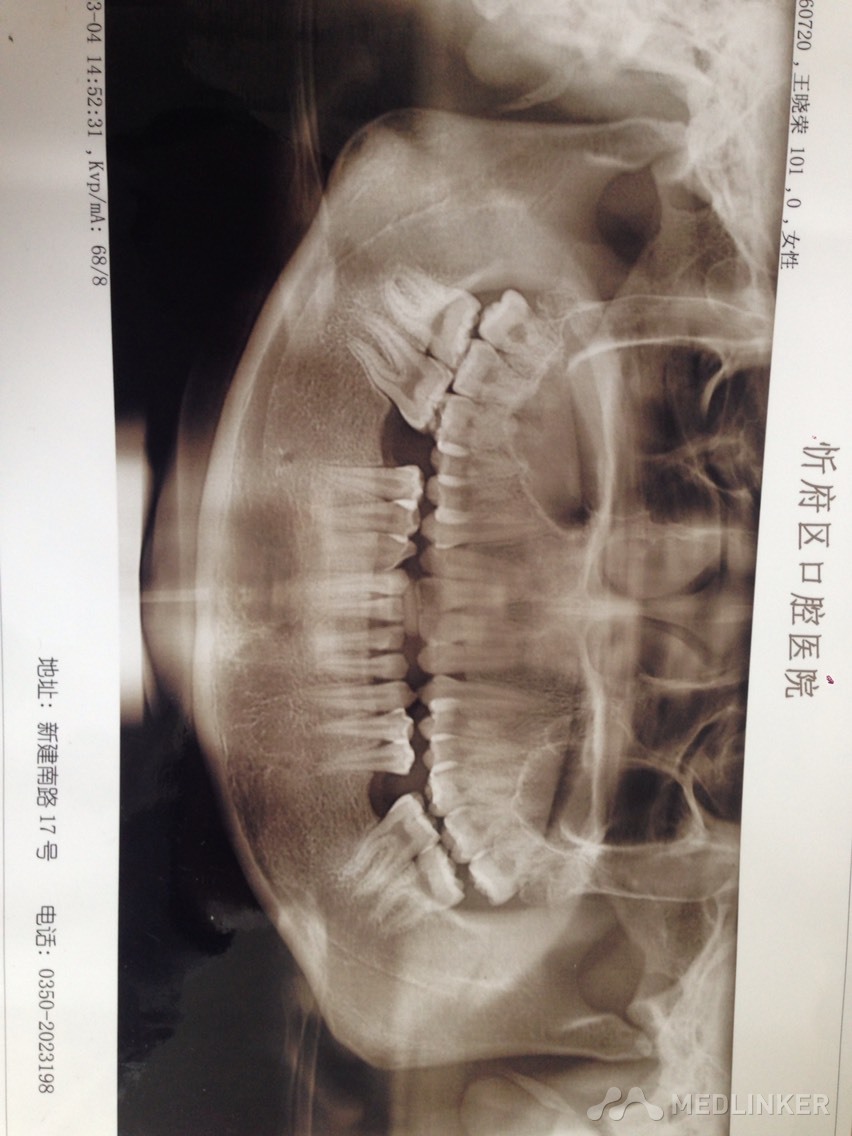

上颌前牙牙列拥挤,下颌前牙散在间隙,下颌双侧第一磨牙缺失多年,开合